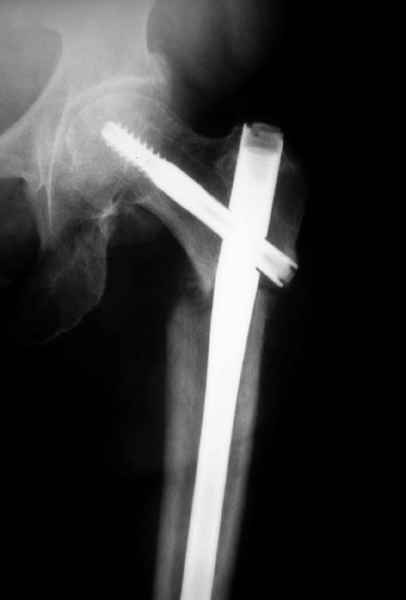

Михаил, здравствуйте. Если присмотреться - на четвертом снимке есть перелом гвоздя по отверстию.

Видимо, проблем тут две: во-1-х, центральный отломок был оставлен в варусно-сгибательной установке, во-2-х, не динамизировали вовремя.

Нижние винты хотели сломаться, но, увы, один не сломался, и тогда сломался гвоздь. Хотя и при динамизации в таком положении отломков

могло не срастись.

Не стали усложнять интрамедуллярным вариантом коррекции, легче контролировать коррекцию пластиной, поэтому сделали операцию 95 градусной Blade Plate, разогнув до 110 градусов.

Надеемся на успех, потому что до введения пластины дефект от импланта забили костной стружкой и удалось создать компрессию между отломками, максимальную для импланта (150 кило/паунд). Сделана дополнительная костная пластика и за счет измененного угла пластины устранено укорочение конечности.